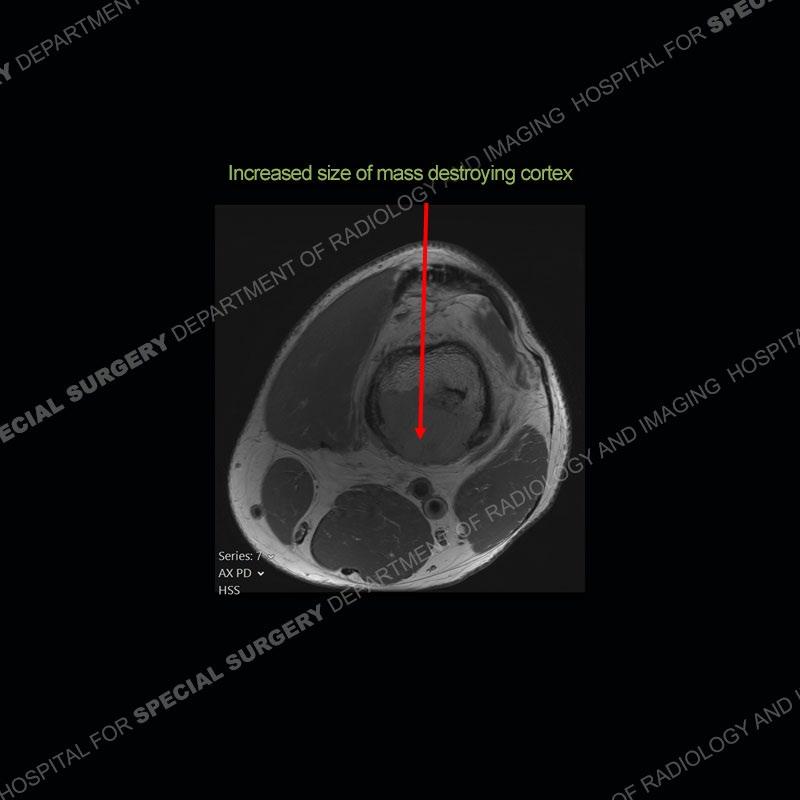

Subsequent imaging of 2024 demonstrates increased size of the mass lesion about the infarct of the distal femur with destruction of the posterior cortex.

Diagnosis: Sarcomatous Transformation of Medullary Infarction

Bone infarcts are fairly common to find and for the most part are asymptomatic. These lesions most typically become symptomatic when they extend to the end of the bone and are associated with subchondral fracture and collapse. Complications of infarct such as infection or sarcomatous transformation are known to occur but because they are extremely rare, exact incidence is not known. Interestingly, most reported cases of sarcomatous transformation occur in middle aged men and about the knee as in this case. Sarcomatous transformation of an infarct can be suggested on radiographs if the infarct goes from being well defined to less well defined. On cross sectional imaging, a destructive mass, as seen in this case, is seen to take the place of the otherwise typical appearance of an infarct. The sarcoma most commonly is an MFH ( more recently delineated as UPS or undifferentiated pleomorphic sarcoma) or osteosarcoma. These sarcomas unfortunately carry a very poor prognosis.